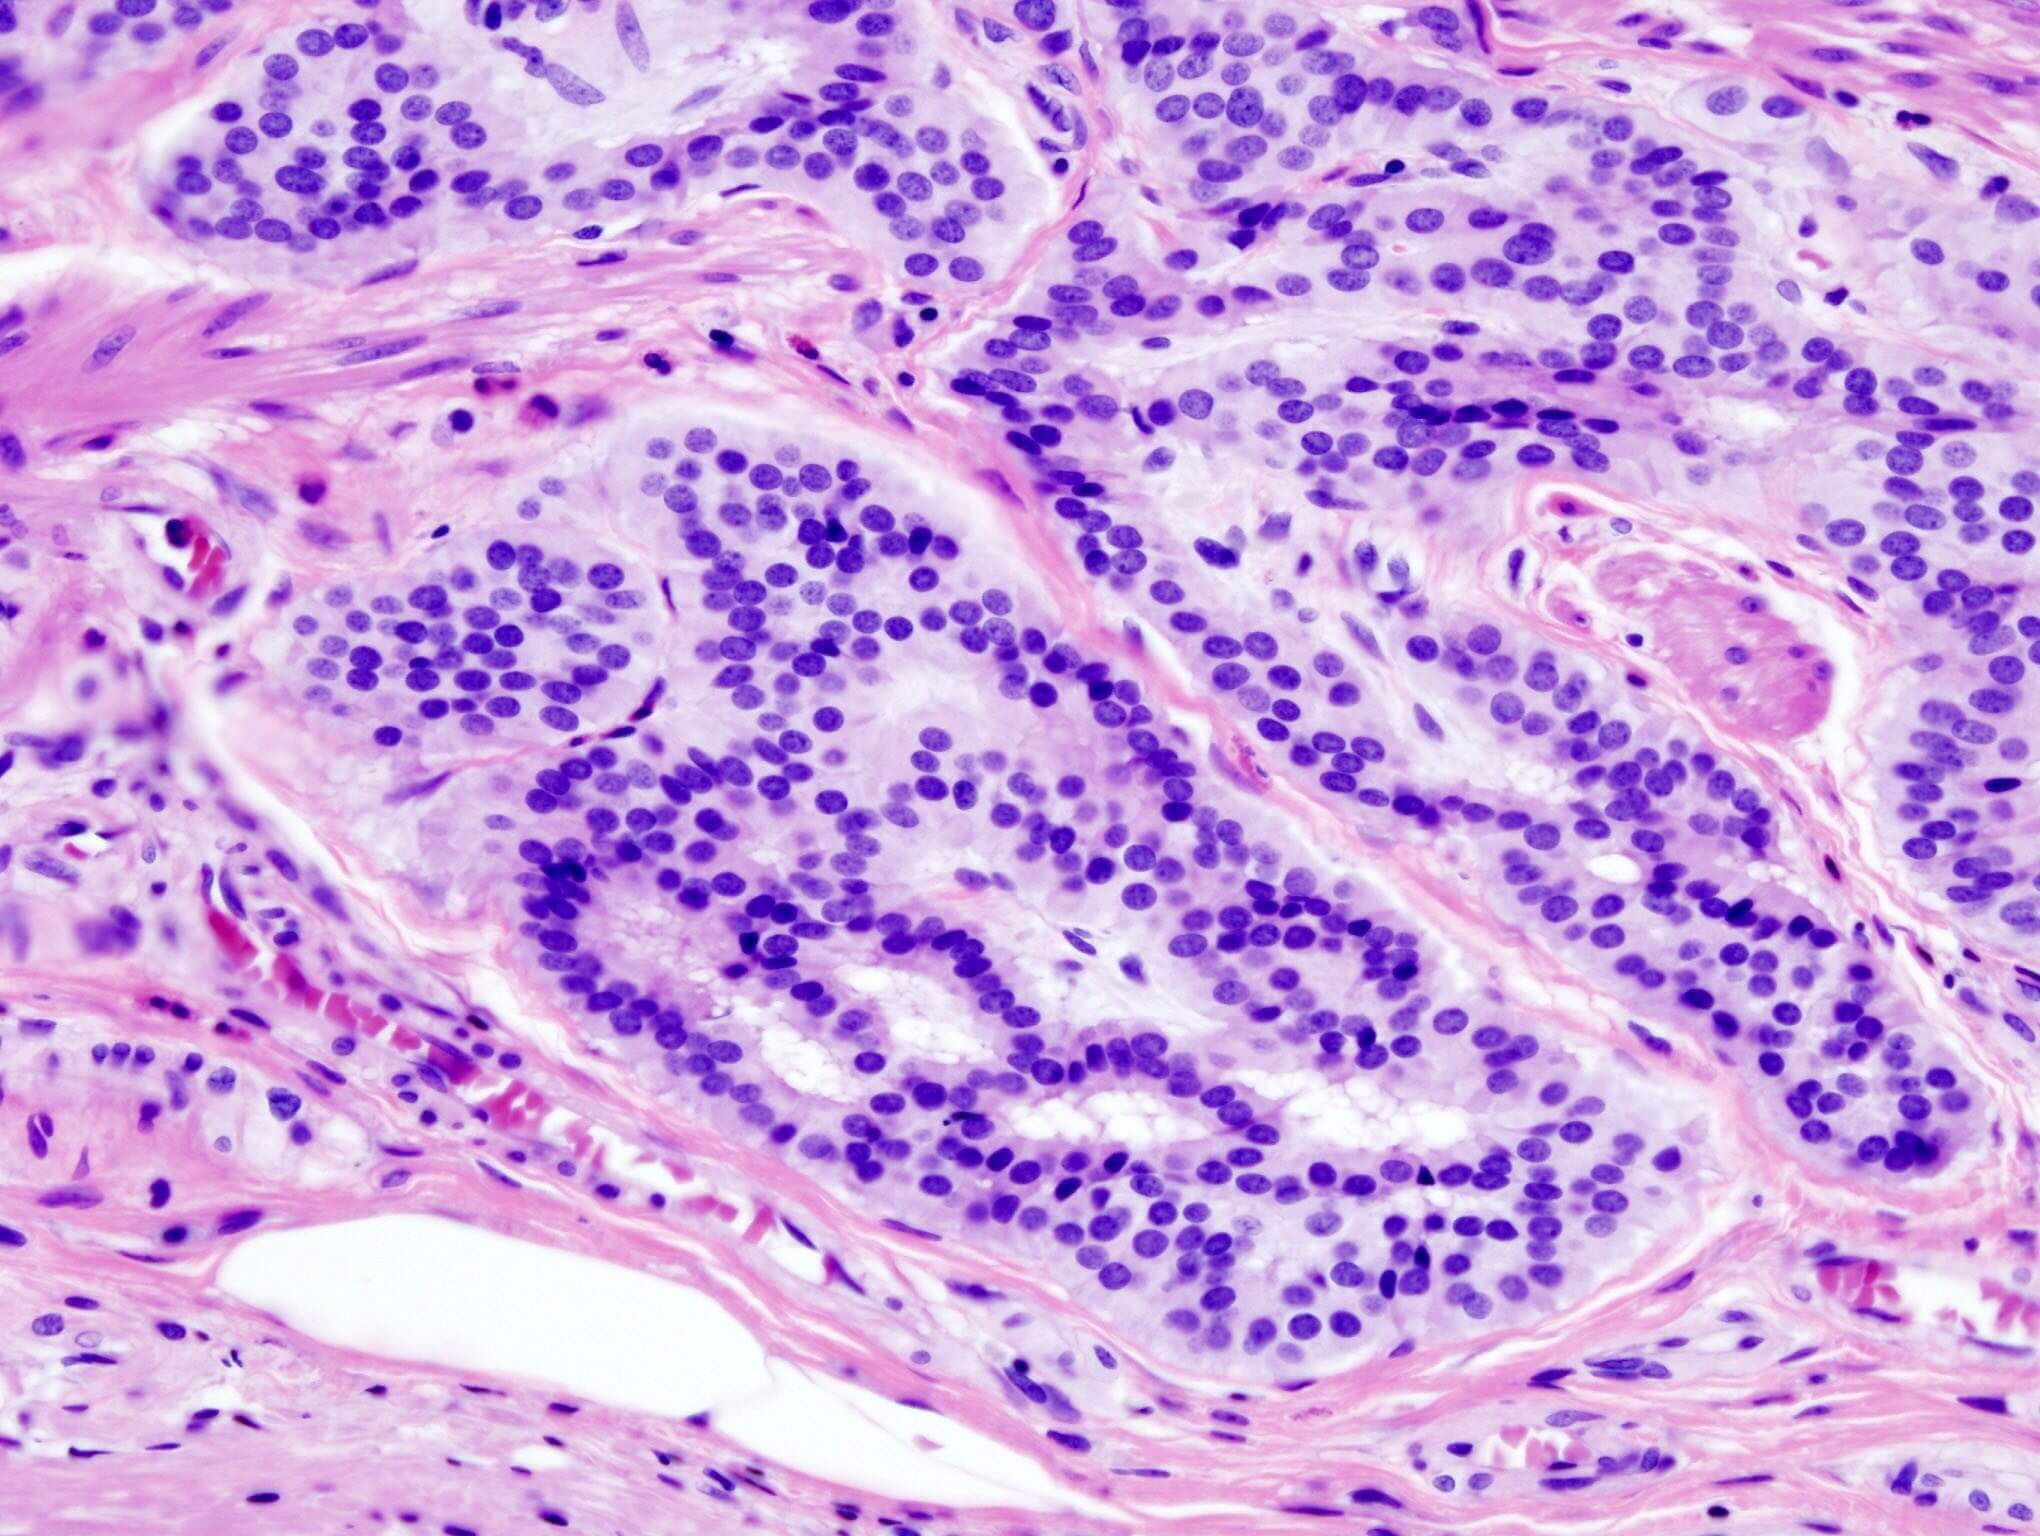

Le terapie CAR-T rappresentano una strategia immunoterapica di ultimissima generazione nella lotta ai tumori ematologici. Utilizzano i globuli bianchi (linfociti T) prelevati dal paziente e appositamente ingegnerizzati per attivare il sistema immunitario; una volta reinfusi nel paziente, entrano nel circolo sanguigno e sono in grado di riconoscere le cellule tumorali e di eliminarle.